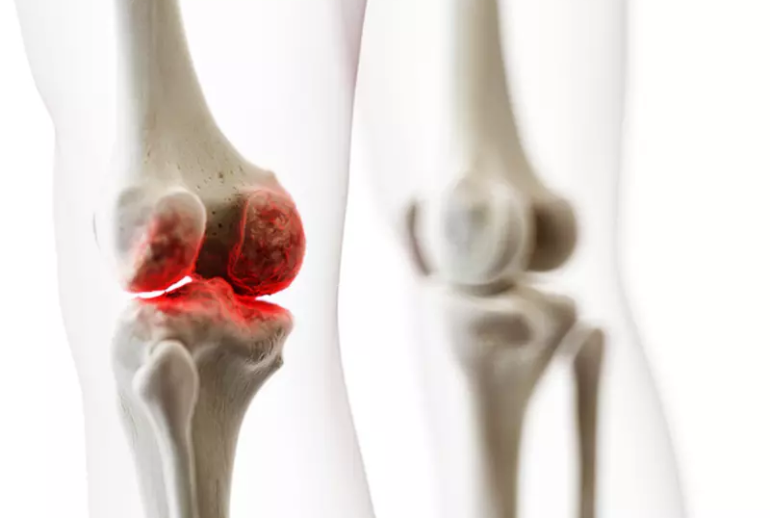

التهاب مفاصل یا آرتریت، به تورم و درد در مفاصل بدن گفته میشود که میتواند به تدریج یا ناگهانی بروز کند. این وضعیت میتواند یک یا چند مفصل را درگیر کند و انواع مختلفی دارد، از جمله آرتروز، روماتیسم مفصلی، نقرس و اسپوندیلیت آنکیلوزان.

- فرسایش و آسیب به غضروفها: این وضعیت بیشتر در آرتروز دیده میشود که به مرور زمان با ساییدگی و تخریب غضروف مفاصل همراه است.

- تورم: تورم در ناحیه مفصل که ممکن است همراه با گرما و سرخی باشد.